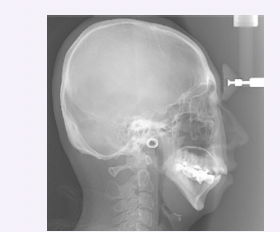

Sickle cell anemia

● Abnormal hemoglobin synthesis resulting in reduced oxygen levels

● Most common in Black Americans

● Moon-shaped red blood cells, swelling of extremities, and episodes of pain during vaso-occlusive crises

● Hair-on-end appearance of the skull, interproximal alveolar bone step ladder patterns

● May experience tonsillitis and adenotonsillar hypertrophy which can lead to airway obstruction and obstructive sleep apnea